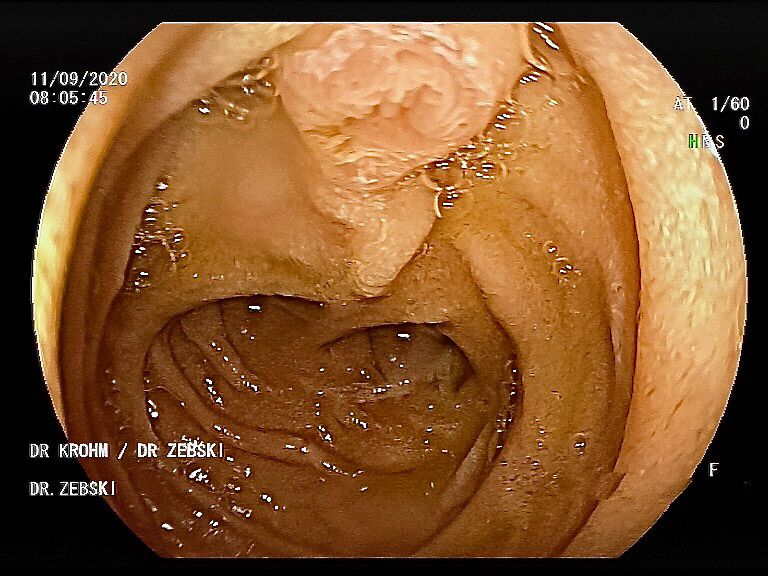

Mit einer Gastroskopie werden Speiseröhre, Magen und Zwölfingerdarm (der oberste Teil des Dünndarms) untersucht. Dazu wird ein geschmeidig biegsames, schlankes Endoskop mit eingebauter Digitalkamera durch den Mund eingeführt. Minimalste Veränderungen können dabei gesehen werden, die im Röntgenbild oder einer Kernspintomographie (MRT) noch gar nicht erkannt werden. Im Vergleich zu anderen bildgebenden Untersuchungsverfahren ist bei der Endoskopie neben der wichtigen optischen Beurteilung auch die sofortige Möglichkeit gegeben, Gewebeproben aus auffälligen Bereichen zu entnehmen. Dazu wird eine kleine Spezialzange durch einen Kanal im Endoskop geschoben und die Probe ganz präzise aus dem entsprechenden Gewebe gewonnen. Da die Schleimhäute schmerzunempfindlich sind, spüren Sie davon nichts. Die Proben werden von Spezialisten mikroskopisch untersucht und ermöglichen dann eine zielgerichtete Therapie; zum Beispiel wenn eine Magenschleimhautentzündung durch eine chronische Infektion ausgelöst wird, die mit einer Antibiotikakur erfolgreich behandelt werden kann.